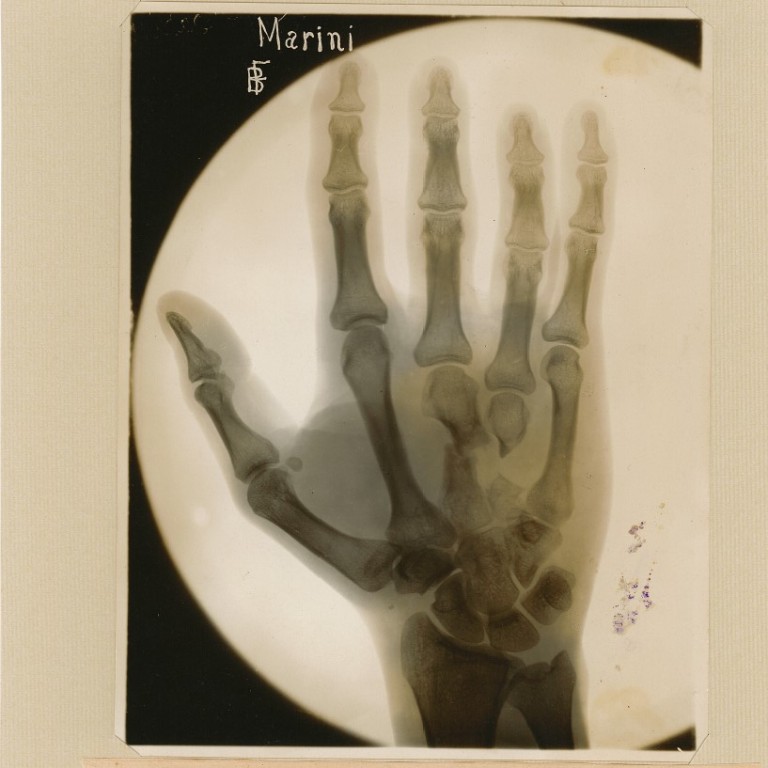

The Ca“ Granda Treasures Museum’ hosts an exhibition dedicated to the history and evolution of the X-rays, on the occasion of the 130 years since their discovery and the 180 years since the birth of Wilhelm Conrad Röntgen. The exhibition, entitled Antique X-ray plates, highlights the first diagnostic and therapeutic applications of X-rays, offering a fascinating overview of history of medicine, science e technological innovation.

On display are ancient X-ray plates, kindly lent by Diocese of Chiavari, next to historical radiogenic equipment belonging to the Marconi-Delpino“ Scientific High School” of Chiavari. To make the experience even more engaging, explanations of the technologies on display are provided by the students of the degree course in Medical Radiology, Imaging and Radiotherapy Techniques of theUniversity of Milan.

The exhibition also pays tribute to the early adoption of X-rays in the Italian hospital context: as early as 1897, at the Policlinico in Milan, Dr. Carlo Luraschi carried out the first X-ray experiments on injured people from the 1898 riots, while in 1904 Dr. Ambrogio Bertarelli introduced the use of X-rays for the dermatological radiotherapy.